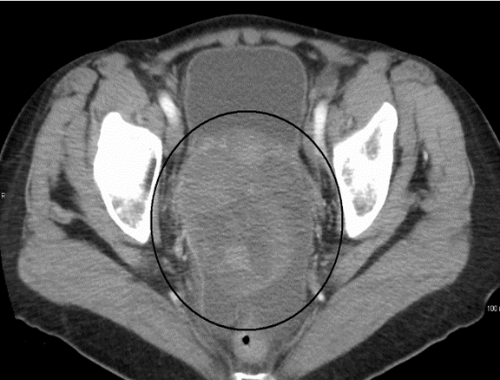

Tomografía de cáncer de ovario